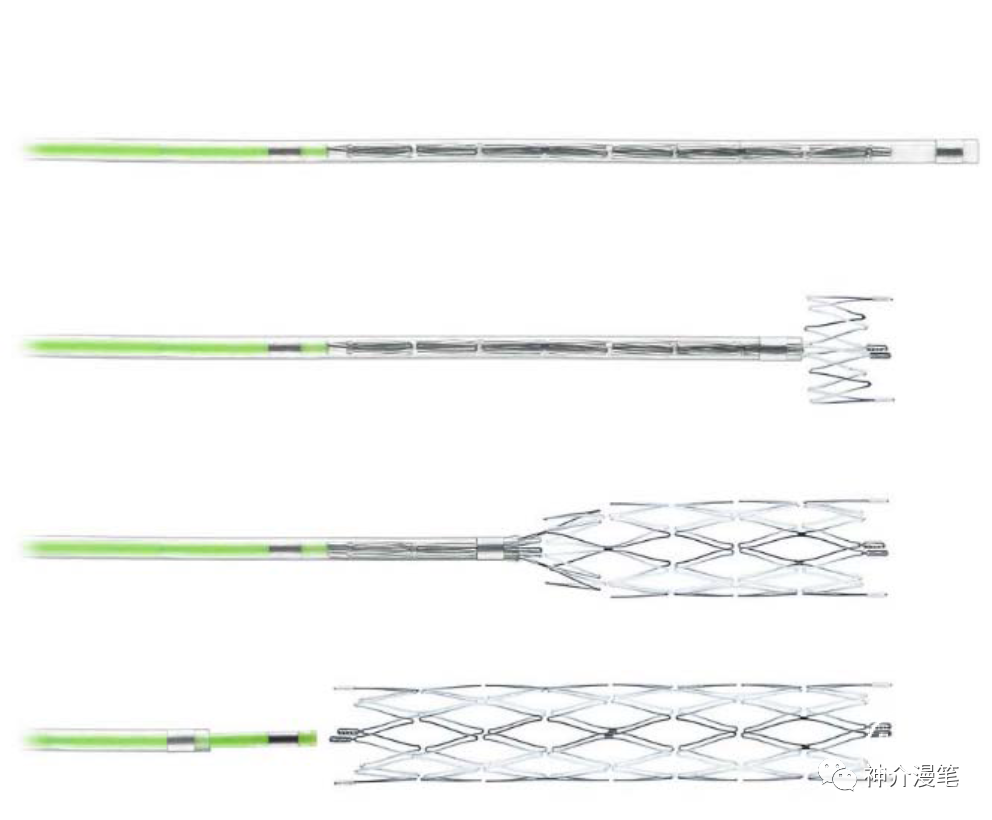

下图为开环支架打开及释放的过程,可以看到每一环支架都会相对独立,而不会过多的影响其他部位打开的情况。所以对于好多新手,我会建议他们早期可以尝试开环支架的释放,因为头端一旦打开就会有比较良好的贴壁性,而不用担心支架滑落。

编织支架在不同管腔内会拉伸,并有释放后短缩现象。雕刻支架:金属圆筒由激光镂空雕刻形成,雕刻支架长度基本稳定,拉伸或短缩的现象极为少见。从结构特点上我们能知道,开环支架全部是雕刻支架,闭环则可能是雕刻也可能是编织。看过我这篇小豆腐块的同志,千万不要再从你们嘴里出现编织开环支架这个词了。下面第一个图,编织闭环支架,第二图为激光雕刻开环支架。

波科 WALLSTENT 支架

Wallstent支架不同于前面两款,自身特点同样突出,关键词:编织支架,闭环支架,自膨支架,是目前主流颈动脉支架中唯一一款编织支架。具备着编织支架普遍共性,在不同管径血管内会被拉伸和短缩,释放难度略高于其他几款支架,但是有更高的金属覆盖率和更小的网眼面积。此外,wallstent支架的显影性是最棒的,这一点用过的可能都知道。

需要提醒大家注意的是,编织支架在不同管径的血管中会出现明显长度的变化,如下表所示。因此选择支架长度时一定要根据目标血管直径来选择合适长度的支架,避免过长或过短,另外wallstent支架释放后会有一定程度的回缩,所以定位支架着陆点时应预留足够测长度,防止支架短缩后无法完全覆盖狭窄造成尴尬的局面。另外需要注意的是,wallstent支架和所有闭环支架一样,在释放时需远端打开一定长度后方能彻底打开贴壁,在此过程中如后手把持的力度不够有可能造成支架下滑。

雅培系列支架

雅培上面两款支架一个开环,一个闭环,应用的场景,使用原则和上诉所说的支架大体差不多,大家可以再看一下他们的具体型号和尺寸。酌情使用,比较有意思的是这两款支架的释放都是“半自动化的”,支架到位后通过旋转释放手柄或回拉把手即可完成。不需要前面几款支架的推扒技术,所以一旦支架到位良好,释放极度简单,几乎就是傻瓜式释放,特别适合新手小白使用。